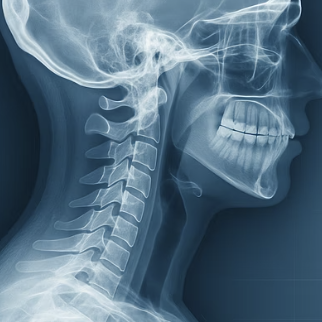

우리 목덜미 뒤쪽에서부터 뒷머리를 거쳐 정수리 부근까지, 전선처럼 넓게 퍼져있는 감각 신경이 바로 ‘후두 신경’입니다. 이 신경은 딱딱한 머리뼈와 뭉친 목 근육 사이의 좁은 터널을 지나가는데, 바로 이 터널에서 문제가 시작됩니다.

우리가 고개를 앞으로 쭉 빼는 거북목이나 일자목 자세를 오래 유지하면, 목덜미 뒤쪽의 근육들이 머리를 지탱하기 위해 비정상적으로 긴장하고 딱딱하게 굳어버립니다. 이렇게 뭉친 근육 덩어리가 신경이 지나가는 길을 꽉 눌러버리니, 신경이 눌리고 자극을 받아 찌릿한 통증과 이상 감각을 만들어내는 것입니다. 따라서 근본적인 해결책은 이 좁아진 길을 다시 넓혀주는 것에서부터 시작해야 합니다.

“고작 고개 좀 숙였다고 그렇게까지 될까?” 싶으시죠. 하지만 우리 목이 감당하는 무게는 상상을 초월합니다. 볼링공 하나 정도의 무게(약 5kg)인 우리 머리는, 고개를 15도만 숙여도 목이 느끼는 하중은 12kg으로, 60도까지 숙이면 무려 27kg의 쌀 한 가마니를 목에 이고 있는 것과 같은 압력을 받게 됩니다.

매일 몇 시간씩 스마트폰을 보며 이런 엄청난 부담을 목에 주고 있다고 상상해 보세요. 목 주변의 근육과 인대가 버텨낼 재간이 있을까요? 결국 만성적인 긴장과 피로가 쌓여 근육은 돌처럼 굳고, 경추의 정상적인 C자 곡선은 무너져 내리며 신경을 압박하는 최악의 환경이 만들어지는 것입니다.